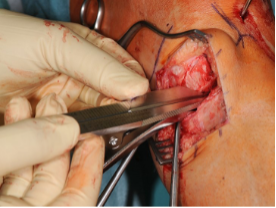

Distal release of the superficial medial collateral ligament

Subperiosteal release of the superficial medial collateral ligament at the tibal insertion is a central element to ensure that the pressure in the medial compartment does not increase with the subsequent opening of the osteotomy [20−21]. The periosteal elevator is used to go below to the superficial medial collateral ligament to the distal and dorsal side and to perform complete subperiosteal release [22] (Rule of thumb: there must be space for one finger width below the collateral ligament) (Fig. 4).

Insufficient release also has the consequence that the osteotomy opens less well on the dorsal side than on the ventral side, which will increase the slope. Thereafter, the periosteum is detached to the dorsal side with the angled periosteal elevator. Then a blunt Hohmann retractor is inserted on the dorsal tibia edge along the osteotomy site to protect the popliteal artery/vein and the tibial nerve.